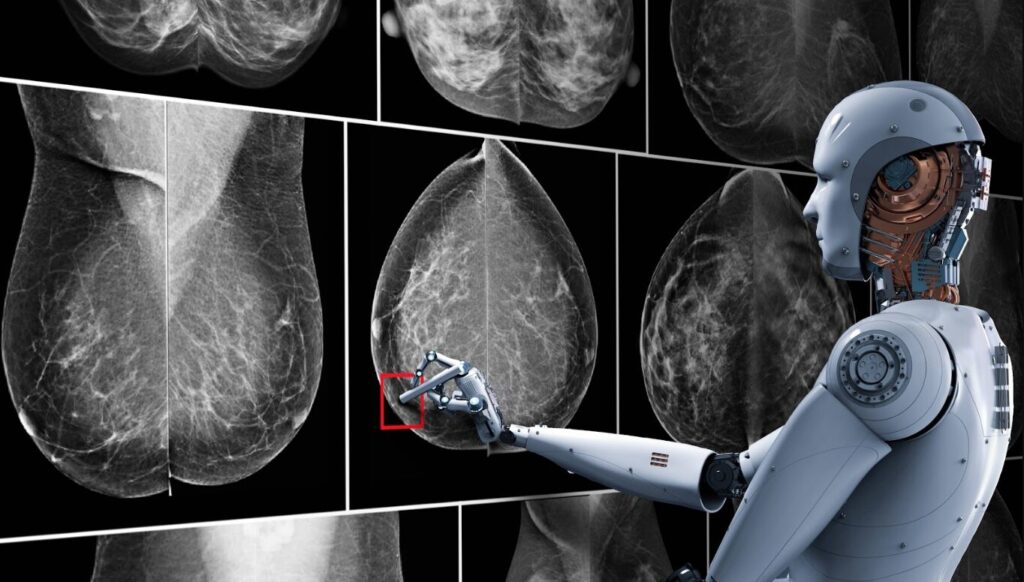

EXPRESO DIGITAL, AUSTRALIA. – Un sistema de inteligencia artificial (IA) desarrollado en Australia podría transformar la forma en que se detecta y se previene el cáncer de mama, al identificar a mujeres con alto riesgo de desarrollar la enfermedad tras recibir una mamografía aparentemente normal, según un estudio publicado este miércoles.

La investigación, publicada hoy en la revista The Lancet Digital Health, analiza una herramienta denominada BRAIx, que utiliza algoritmos de aprendizaje profundo para analizar imágenes mamográficas y calcular una puntuación individual de riesgo de cáncer de mama en los años posteriores al examen.

A partir de sus mamografías, los investigadores calcularon el llamado índice de riesgo BRAIx, una puntuación que estima la probabilidad de desarrollar cáncer en el momento del cribado o en los cuatro años siguientes.

Según los autores, una de las ventajas de este enfoque es que la IA puede extraer señales de riesgo directamente de la imagen mamográfica, lo que permite estimar el riesgo futuro con mayor precisión que factores tradicionales como la densidad mamaria, la edad o los antecedentes familiares.